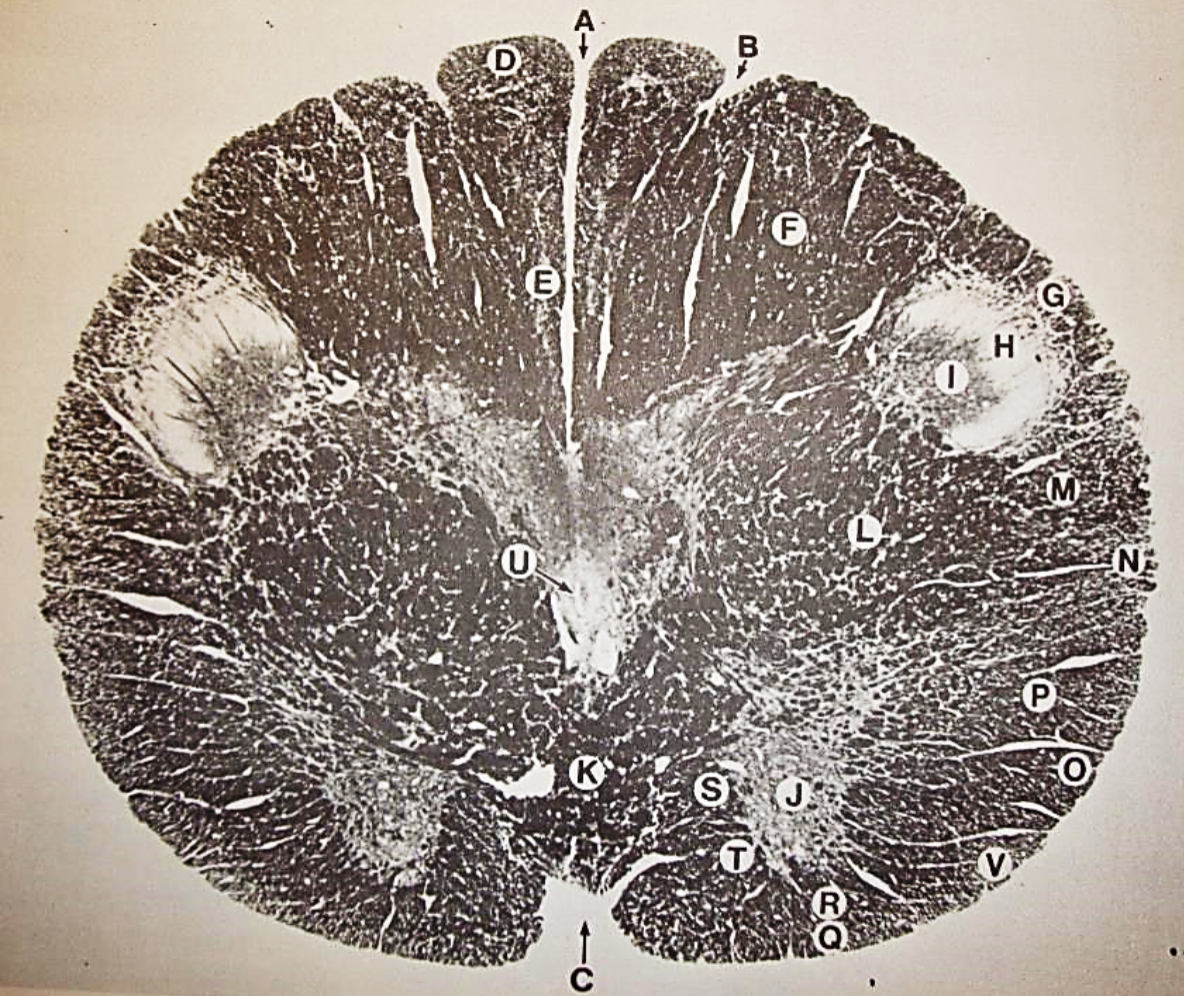

A

Lateral Cuneate nucleus

B

dorsal external arcuate fibers

C + D collectively

vestibular nuclei

C + D collectively

vestibular nuclei

E

dorsal motor nucleus of vagus nerve

F

solitary fasciculus

G

solitary nucleus

H

nucleus ambiguous

I

fascicles of glossopharyngeal nerve

J

hypoglossal nucleus

K

fascicles of hypoglossal nerve

L

dorsal longitudinal fasciculus

M

central tegmental tract

N

inferior olivary nucleus

R

inferior cerebellar peduncle

S

spinal trigeminal tract

T

spinal trigeminal nucleus

U

ventral trigeminothalamic tract

V

pyramidal (corticospinal) tract

W

rubrospinal tract

X

anterior spinocerebellar tract

Y

spinal lemniscus

Z

medial longitudinal fasciculus

a

tectospinal tract

b

medial lemniscus

c

vagus nerve

d

inferior salivatory nucleus